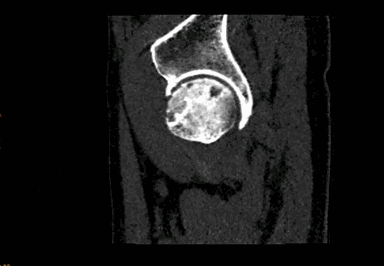

病例1:髋关节4D成像。Revolution CT 采用16cm探测器覆盖范围的连续扫描即可得到关节动态图像。此临床应用目的为鉴别撞击综合症和股骨头坏死。